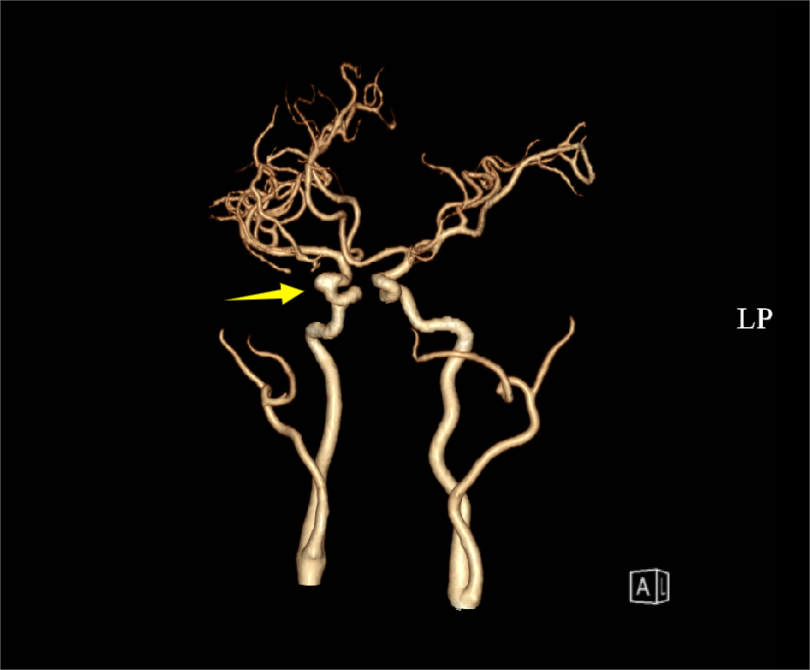

與患者充分溝通后,治療團(tuán)隊(duì)為陳女士進(jìn)行了腦血管介入手術(shù),術(shù)中行腦血管造影,明確動(dòng)脈瘤位于右側(cè)頸內(nèi)動(dòng)脈眼段,呈囊狀,與術(shù)前判斷一致。最終,在麻醉科、介入導(dǎo)管室科等相關(guān)科室的通力協(xié)作下,治療團(tuán)隊(duì)采用微創(chuàng)介入治療方式成功將Surpass Evolve血流導(dǎo)向密網(wǎng)支架覆蓋于動(dòng)脈瘤處,一小時(shí)即完成手術(shù),術(shù)后患者無不適,恢復(fù)良好。

術(shù)后血管造影